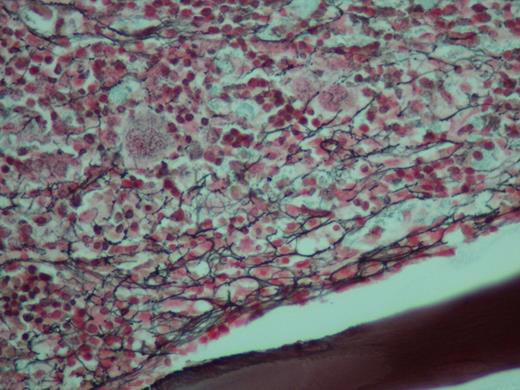

Reticulin stain of biopsy showing a moderate to marked increase in coarse reticulin fibers